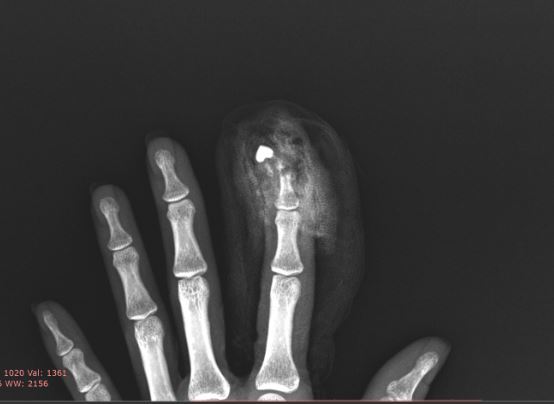

30대의 김@@님은 근무하시다가 기계에 끼이는 사고로 인해 왼쪽 검지에 부상을 입으셨습니다.

제 2수지 불완전 절단

압궤손상 및 개방성 분쇄골절

특히 개방성 골절은 골절된 골편이 피부 밖으로 드러나게 되기 때문에 세균 감염의 위험과 수술하고 나서도 골절의 범위와 단면에 따라 단순 골절과는 달리 운동 범위가 제한되거나 골손실 등 후유증을 야기할 수 있습니다.